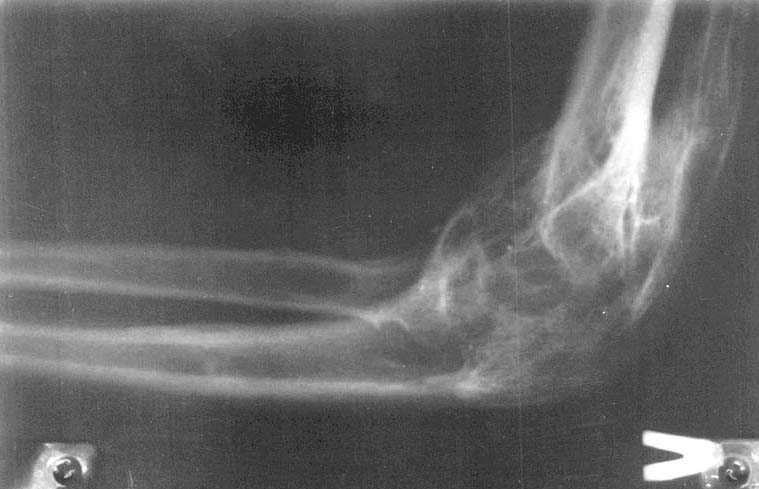

Из одного из городов нашей области к нам обратились родственники пациентки с вопросом о возможности оперативного вмешательства на локтевых суставах.К сожалени, мы ничего предложить не смогли. Ваше мнение? Каким может быть дальнейшее (оперативное, консервативное) лечение?

Женщина, 22 года, инвалид 1-й группы. В анамнезе парезы и плегии из-за разрыва аневризмы головного мозга и последующего ишемического спазма сосудов головного мозга при повторной операции. Дз: остаточные явления обширной двусторонней ишемии мозга вследствие оперативного вмешательства по поводу аневризмы ПСМА (2001 г.), нижний глубокий спастический парапарез, нейрогенные дисфункции тазовых органов, контрактуры локтевых, коленных и голеностопных суставов.КТ головного мозга: кистозно-атрофические изменения в обеих лобных долях (без динамики с 2002 г.), постинсультная киста в области колена внутренней капсулы базальных ядер справа, гипотрофические изменения в полушариях большого мозга.